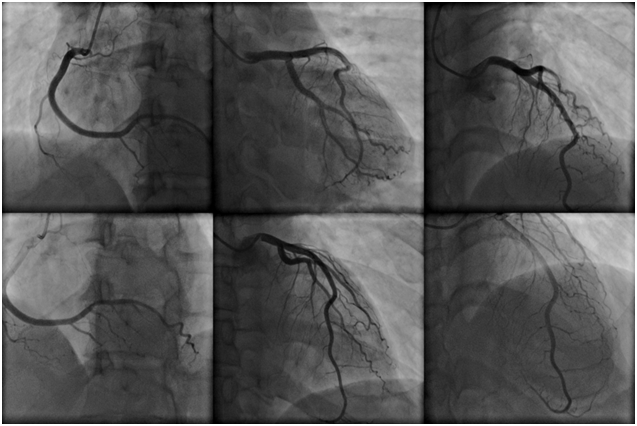

Внизу – так выглядят коронарные артерии на коронарограммах

Иглой пунктируют бедренную артерию на ноге (в верхней трети бедра) или на руке (лучевую артерию на предплечье около запястья или плечевую артерию). По специальной методике в артерию вводят катетер называемый интродьюсером. Под рентгеновским контролем длинный катетер через интродьюсер по направляющей (проводнику) подводится к устью коронарной артерии, устанавливается непосредственно (селективно) в устье артерии. По катетеру селективно в коронарную артерию вводится рентгеноконтрастное вещество. Одновременно с этим, выполняется ряд рентгеновских снимков в разных проекциях (под разными углами), что позволяет увидеть внутренние контуры артерии с местами сужений (стенозов) и расширений, с местами закупорки артерий (окклюзий) и пристеночными тромбами; позволяет оценить состояние атеросклеротических бляшек (осложнённые, разорванные, расслоенные и т.п.).

Коронарография — это инвазивный (т.е. связанный с проникновением внутрь организма) рентгеноконтрастный метод исследования артерий сердца, позволяющее увидеть внутренний контур артерий сердца на рентгеновском изображении. Метод основан на том, что к артерии сердца (коронарной артерии) подводится катетер (катетер представляет собой тонкую и гибкую полую трубку), через которую внутрь коронарной артерии вводится специальное контрастное вещество, распознающееся рентгеновскими лучами. Общий вид исследуемых сосудов при просвечивании рентгеном выводится на монитор специальной компьютерной техники. На данный момент коронарография является «золотым стандартом» в качестве диагностики заболеваний артерий сердца.